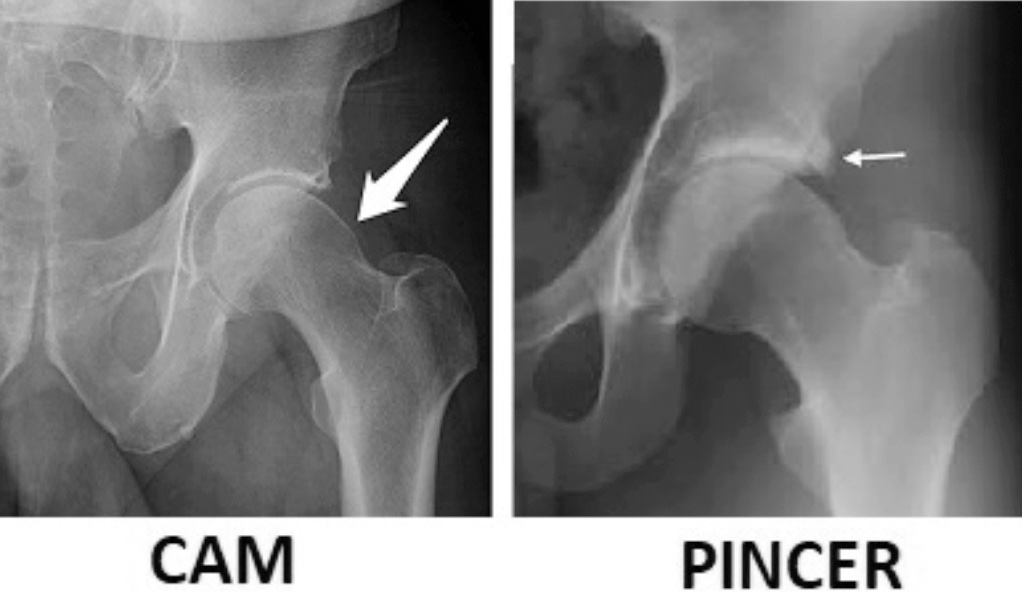

Oltre a queste malformazioni maggiori che possono determinare un’artrosi secondaria dell’anca, negli ultimi anni si è affermato il ruolo dell’impingment femoro-acetabolare (FAI) 4 come fattore patogenetico fondamentale nello sviluppo della patologia anche nelle forme precedentemente considerate “idiopatiche”. Il FAI viene diviso in due forme, quella CAM ove vi è una alterazione della giunzione collo-testa femorale che determina una alterazione della sfericità della testa, e in quella PINCER, dove invece è il bordo acetabolare ad essere prominente causando attriti e lesioni durante il ROM (Fig. 1).